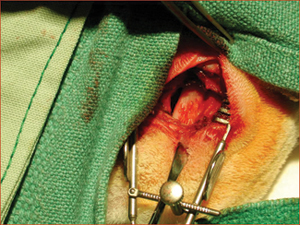

The protocol for the study was approved by the University of Toronto Animal Care and Ethics Committee (protocol 20003105). Forty adult male New Zealand white rabbits (Charles River Laboratories, Wilmington, MA), weighing 3.5 to 4 kg, were randomly divided into 2 groups of 20 animals each, one designated to undergo sacrifice at 2 weeks and the other to undergo sacrifice at 8 weeks. A veterinarian induced general anesthesia, and bone was harvested from the right posterior iliac crest of each animal. A maxillary sinus lift procedure was then performed using an extraoral lateral-window approach (Fig. 1). A round diamond bur was used to outline the lateral wall of the maxillary sinus, and the sinus membrane was then elevated from the sinus floor. One of 5 possible materials was placed onto the sinus floor:

• autogenous bone graft from the posterior iliac crest (Fig. 2)

Figure 1: Maxillary sinus of a rabbit exposed bilaterally to receive bone graft or bioimplant.

Figure 2: Posterior iliac crest of a rabbit exposed for harvesting of material for autogenous bone grafting.